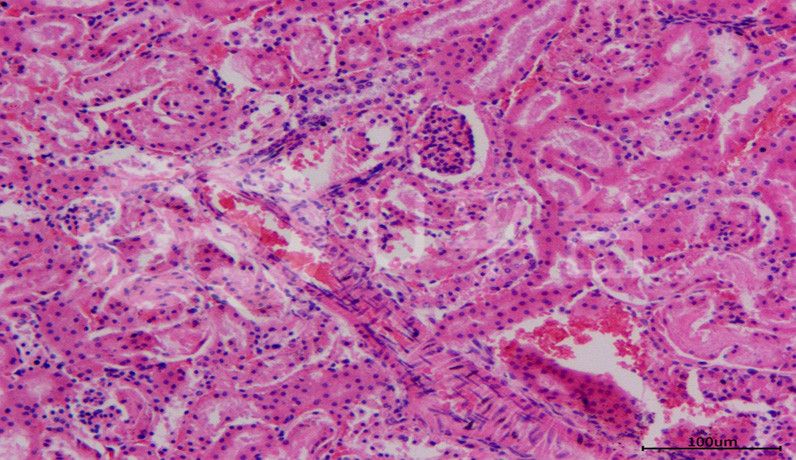

HE染色實操注意事項由普拉特澤生物旗下科研培訓(xùn)品牌《春風(fēng)學(xué)院》總結(jié)分享,文尾附有HE染色視頻教程供大家學(xué)習(xí)。蘇木精—伊紅染色法簡稱HE染色法,是最常用的普通染色方法,普拉特澤生物病理實驗平臺在大量的實戰(zhàn)中積累了豐富的經(jīng)驗,快來聽聽分享吧!